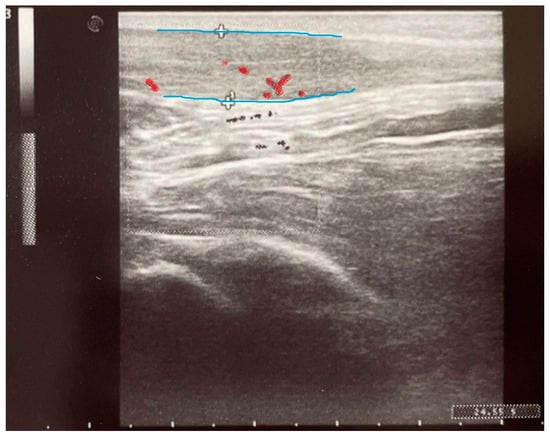

2.4. Paraclinical Evaluation—Ultrasound